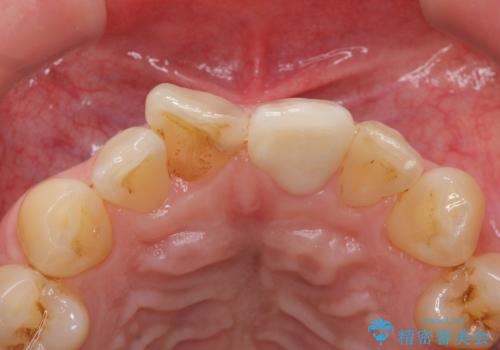

- 前歯のプラスチックの詰め物が気になると来院された患者様です。

左上の前歯に詰められたプラスチック(コンポジットレジン)は、劣化し変色していました。

レジンを除去したところ二次う蝕を認めたため、丁寧に虫歯をとりました。

歯の欠損範囲が大きいことから、同様にレジン修復しても欠けやすいためセラミッククラウンによる補綴を行いました。